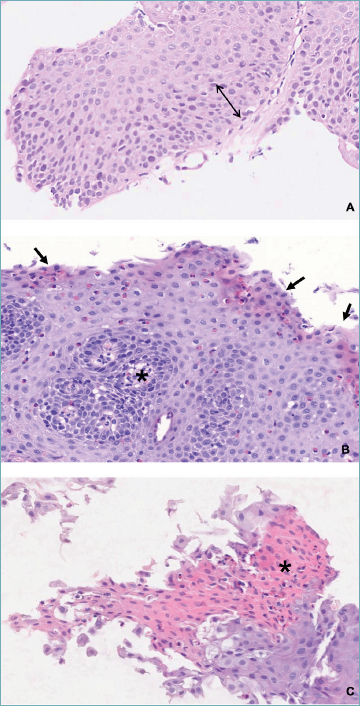

Figure 2. Basal zone hyperplasia and surface epithelial alterations. (A) Double arrow indicates the expansion of the basal zone, which extends to approximately 30% of the whole thickness of the epithelium. (B) Arrows indicate surface epithelial alteration, highlighted by the red appearance of epithelial cells. Asterisk shows the lamina propria within a papilla. (C) Asterisk indicates severe surface epithelial alteration.

- - Basal zone hyperplasia (BZH) represents the reparative response of oesophageal epithelium to chronic injury and inflammation28. Under normal conditions, the basal cell layer constitutes approximately 15% of the total epithelial thickness; however, in EoE, it frequently expands to more than 20-30%24 (Figs. 1E, 2A, and 2B). This thickening results from increased proliferation of basal keratinocytes driven by inflammatory cytokines, particularly those released by eosinophils and other immune cells30. Although BZH is not specific to EoE, in this context, its severity can increase and involve the entire epithelial thickness. It provides strong supportive evidence for EoE diagnosis when associated with marked eosinophilic infiltration. In cases where BZH is mild and confined to the lower third of the epithelium (typically < 30% of the epithelial thickness), proper biopsy orientation is essential for accurate evaluation. BZH also contributes to mucosal remodelling and compromises epithelial barrier function, thereby increasing susceptibility to antigen penetration and perpetuating chronic inflammation24.

- - Superficial epithelial alteration (SEA) is characterised by changes in the tinctorial properties of the oesophageal epithelium, manifesting increased eosinophilic staining (darker red appearance) of the surface epithelial cells10 (Figg. 2B and 2C). These alterations may be observed with or without an associated eosinophilic infiltrate. SEA is considered a marker of early epithelial injury, may reflect mucosal barrier dysfunction, and has been proposed as a marker of lamina propria fibrosis (LPF) (see below)31. Another potentially occurring feature is dyskeratosis, defined as aberrant or premature keratinisation of epithelial cells, indicating cellular stress or chronic injury10.